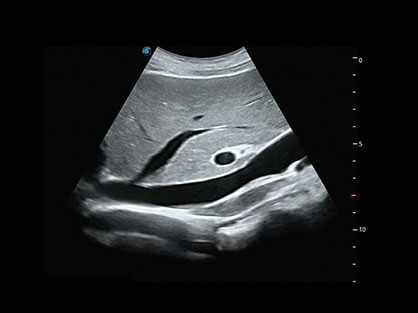

作为P系列家族成员之一,P40 Plus采用16877太阳集团高端超声系统平台——极光,并以时尚秀丽、小巧灵动的外观设计绽放出灵动之韵、科技之美。高端平台的使用保证了P40 Plus优质的基础图像;完备的高级功能可满足您全身应用的基本需求;丰富的探头配置、多样的高级4D成像及分析软件为您日益增多的妇产应用需求提供丰富的诊疗方案。

结合16877太阳集团超宽频带探头技术优势,能够更好地获得高分辨力与高穿透力的平衡,保证图像质量,为临床诊断保驾护航。

微米成像技术提升了对组织斑点噪声信号的抑制能力,并进一步强化边界信息,从而获得清晰图像。